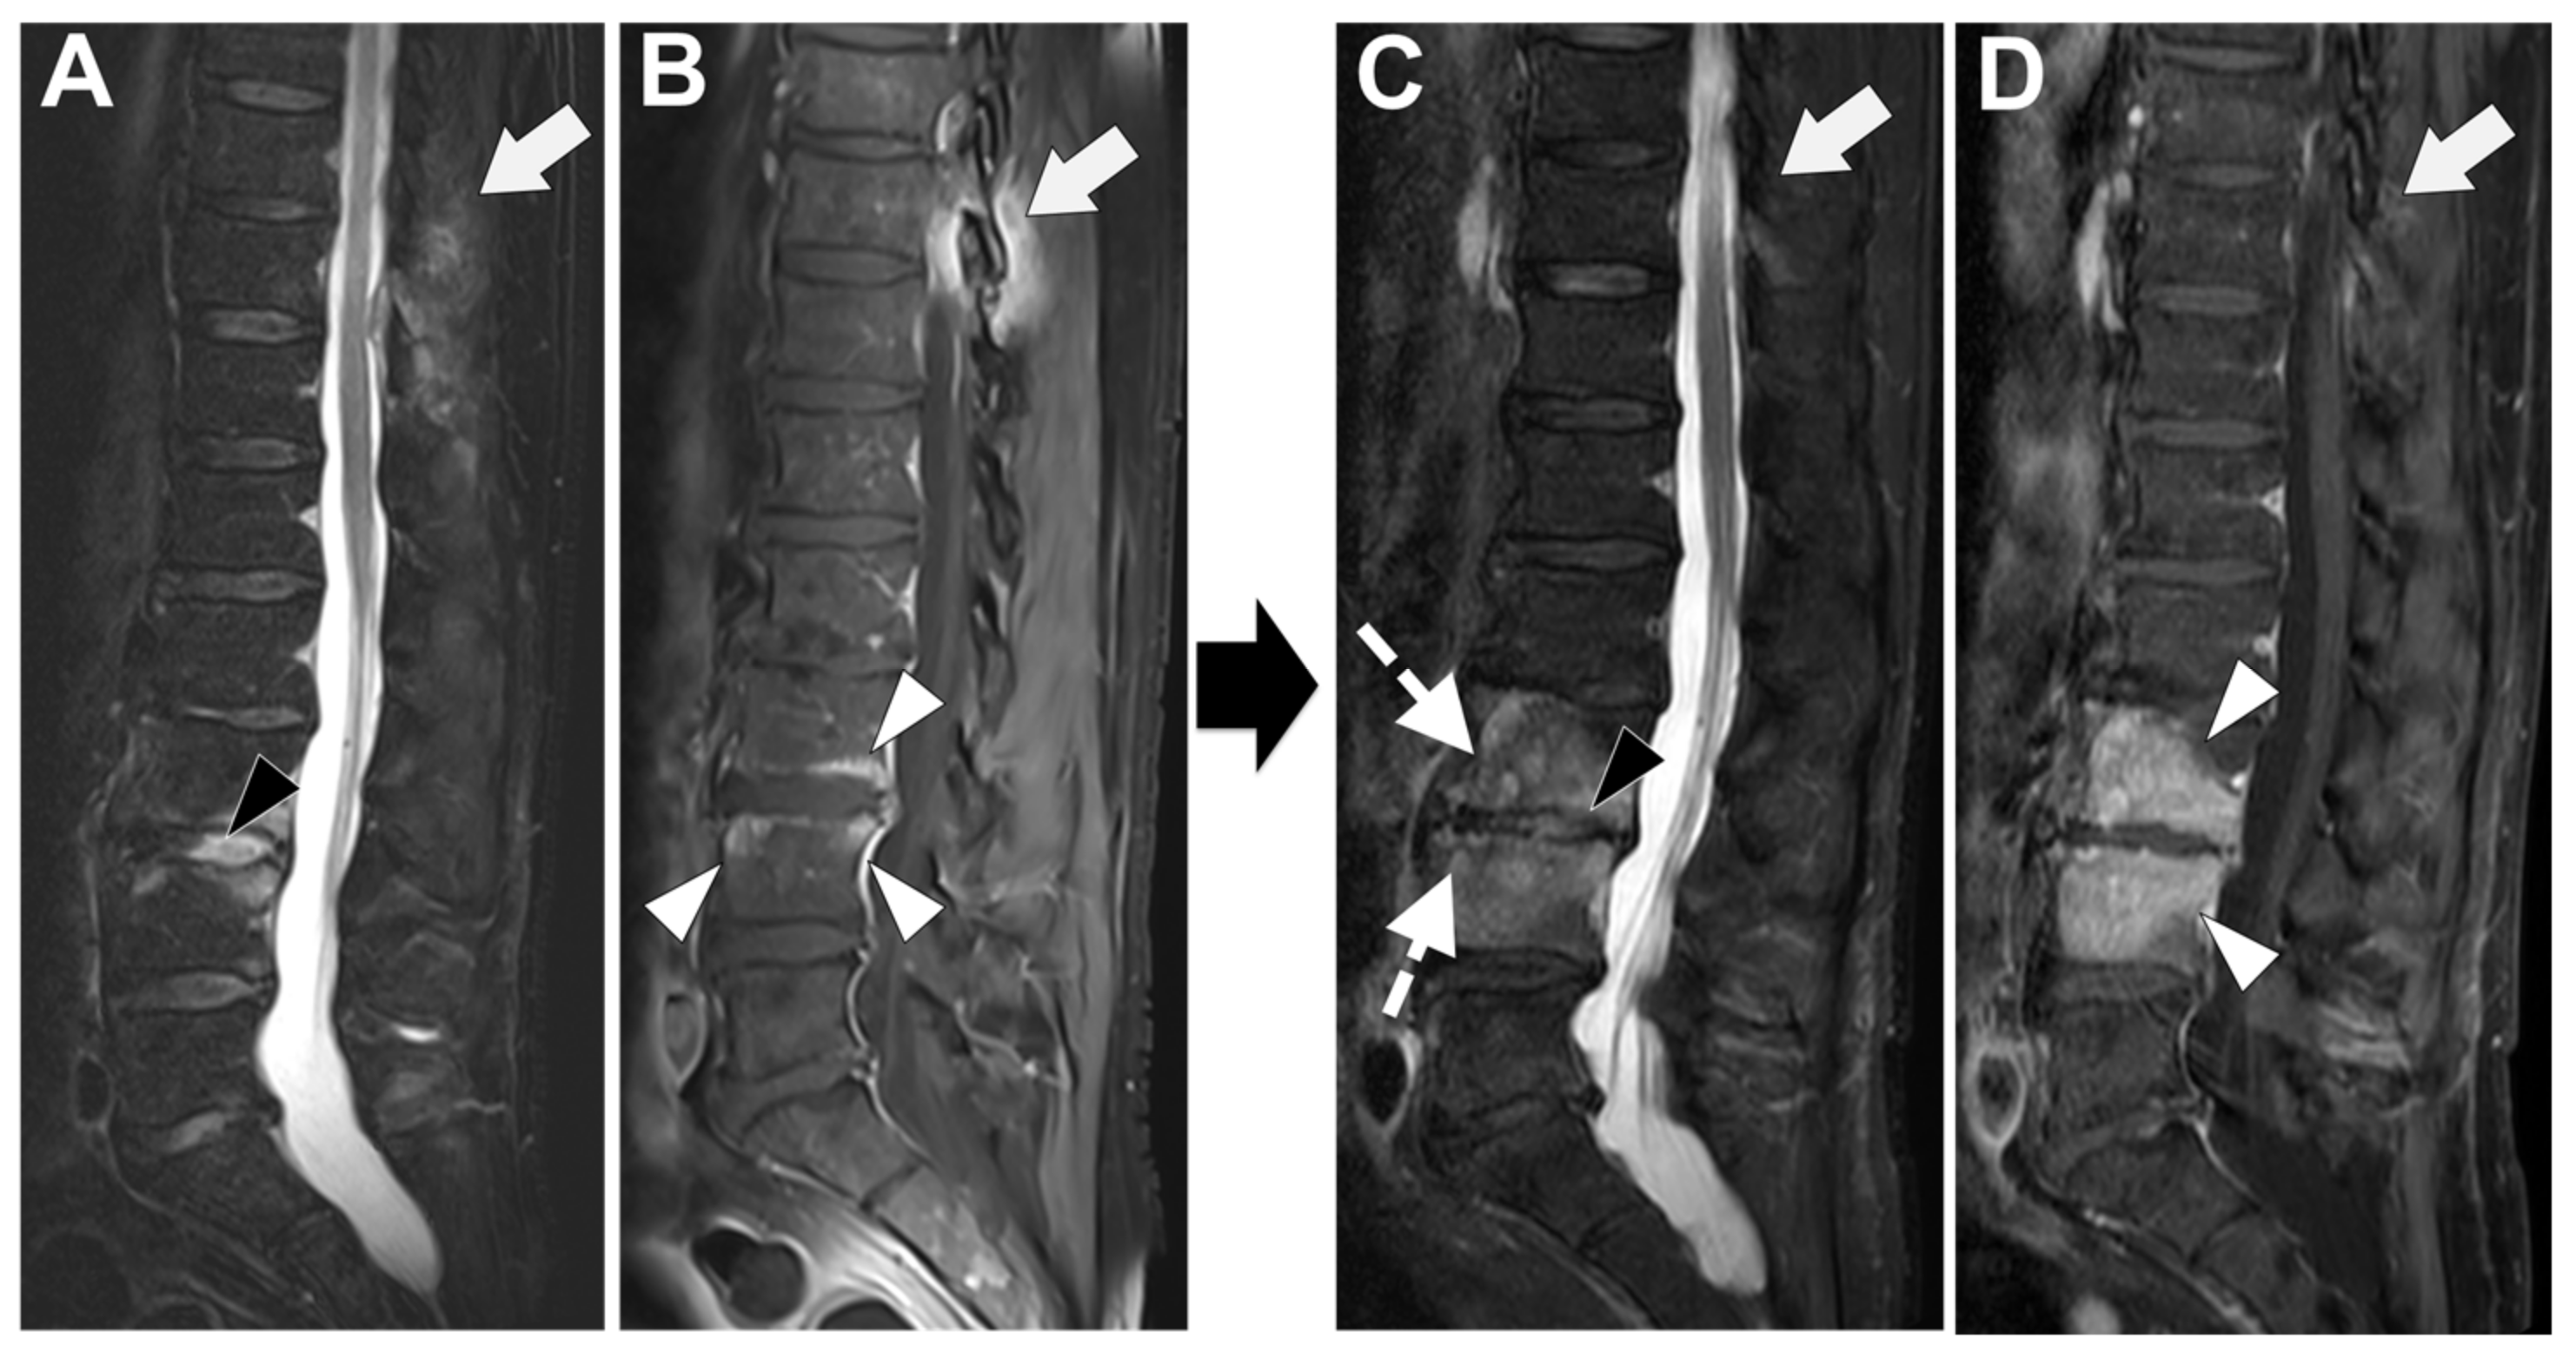

Degenerative end plate changes at the early inflammatory phase (Modic 1) can demonstrate some similar radiological features with infectious spondylodiscitis [72,73], that is to say, irregular end plate contours, possible subchondral cysts, and vertebral edema with a horizontal orientation (with high signal intensity on T2-WI—more pronounced with fat suppression method, low signal intensity on T1-WI, and, when performed, possible contrast-enhancement)—Figure 9.

Figure 9. A 56-year-old male presented with a chronic and mechanic lumbar pain. An MRI was performed with (A) T1-weighted imaging (WI), (B) T2-WI, and (C) fat suppressed T2-WI. It demonstrates multiple Schmorl nodes (arrowheads) and a linear high signal intensity (SI) of the subchondral bones on both side of the L2-L3 level (arrows). There was no erosion, small anterior osteophyte, and degenerative disks. Hence, Modic 1 was diagnosed.